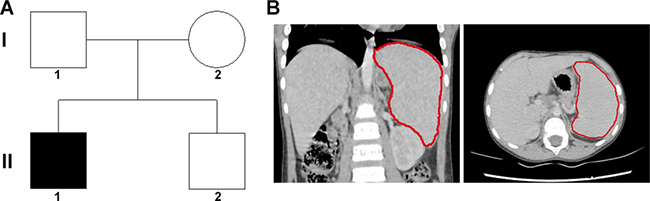

An 8 years old male patient with anemia, jaundice, and splenomegaly, received splenectomy due to severe anemia although only 10% spherical-shaped erythrocytes on the peripheral blood smear. The family tree was drawn (Figure 1A), and the splenomegaly identified by CT scanning was shown in Figure 1B. The changes of RBC and Hemoglobin of the patient with HS pre/post-surgery was recorded in Table 1, and the anemia was ameliorated after splenectomy.

Figure 1: Family tree and clinical characteristics of the patient. (A) the family tree of a Chinese family with patient of HS. A filled square was patient, and unfilled square or circle denoted unaffected male or female respectively. (B) the re-constructed CT scanning image, and the red line outlined the spleen.